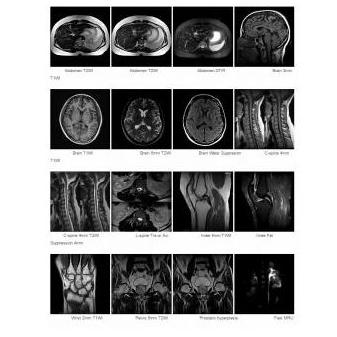

Rezonans magnetyczny MRI OPENMARK 4000 0.4T

OPENMARK 4000  0,4T MRI to model opracowany przy  współpracy ANKE z ANALOGIC Corp., dzięki czemu osiągnięto przełom, uzyskując jakość obrazowania na najwyższym poziomie. OPENMARK 4000 jest rezonansem otwartym, wyposażonym w wydajny układ gradientowy.

• Platformy: sprzętowa i programowa zapewniają szybkie skanowanie, dając przy tym wysoką jakość obrazu oraz dostęp do zaawansowanych funkcji obrazowania.

• Bogata sekwencja skanowania, zaawansowana technologia przetwarzania obrazu i post-processingu zapewniają wysoką jakość obrazu.

• Wiele aplikacji, zaspokajających potrzeby kliniczne.